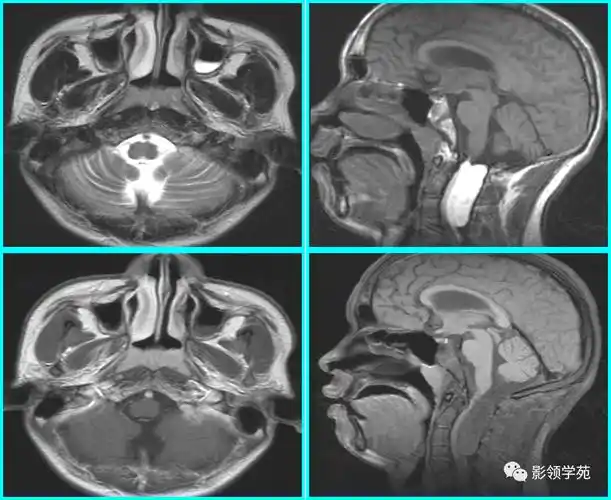

腺样体肥大,肥大的腺样体阻塞90%以上气道

重度腺样体肥大一例

儿童腺样体肥大影像表现及诊断标准